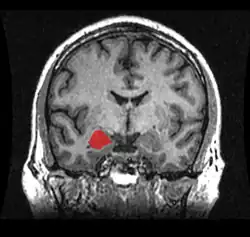

A agressão impulsiva é definida como um ato hostil em resposta a um estímulo percebido como ameaçador ou frustrante.[8] Este tipo de agressão apresenta um forte componente emocional e uma elevada excitação autonômica, além de estar associado a um reduzido controle de impulsos e a uma percepção de hostilidade enviesada.[3] Este tipo de agressão é, geralmente, associado à raiva, o que o coloca em oposição à agressão premeditada.[2] Em termos neurobiológicos, este tipo de agressão apresenta um alto componente amigdalar e reduzido controle de cima para baixo e de funções do Córtex Pré-Frontal.[3] A agressão sem motivo algum denomina-se "agressão gratuita" e é conhecida legalmente como constrangimento ilegal.

As bases neurais da agressão têm sido consistentemente estabelecidas nos últimos anos, onde regiões cerebrais e neurotransmissores, bem como as suas ligações com diversos genes, hormônios e transtornos psiquiátricos, têm sido triadas.[3][7] Dentre as estruturas corticais, o Córtex Pré-Frontal (CPF) é a região cerebral mais amplamente associada com a agressão impulsiva em humanos. O CPF desempenha um papel central no controle de comportamentos, no direcionamento a metas e na tomada de decisões. Pacientes com lesões no CPF ventromedial (CPFvm) tiveram uma maior probabilidade de mostrar confrontos verbais e agressividade, se comparados com pacientes com lesões em outras áreas cerebrais e com grupo-controle sem lesões.[19] Homens com transtorno de personalidade antissocial têm mostrado alterações no COF, no Córtex Cingulado Anterior (CCA), na Insula e na Amígdala. Similarmente, pacientes com Transtorno de Personalidade Borderline e Transtorno Explosivo Intermitente também apresentam características de funcionamento atípico nessas regiões. Estudos de neuroimagem têm confirmado uma disfunção e redução no volume do COF, CCA e CPFvm em pessoas com comportamento agressivo.[20][3]

Um número crescente de evidências tem corroborado a função da amígdala como uma das regiões cerebrais mais importantes para agressão na espécie humana. A amígdala, envolvida no processamento de estímulos biologicamente relevantes e reações emocionais, e o CPF, são reciprocamente conectados.[7][3][20] Além disso, neurotransmissores como serotonina, GABA e dopamina, e hormônios como testosterona, progesterona, cortisol e vasopressina, apresentam um relevante papel determinante para a manifestação do comportamento agressivo.[3]